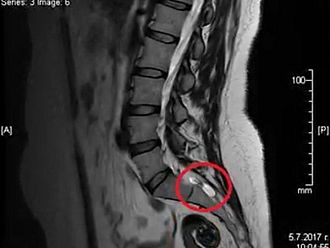

У нас пациентите с периневрални кисти на Тарлов, които членуват в организацията, са 233, но вероятно има и много недиагностицирани случаи. По епидемиологични данни заболяването засяга 5% от населението по света, но се изявява със симптоми при 1%. В 95% от случаите засегнатите са жени. Проявите му нерядко водят до продължителна неработоспособност, затруднения в придвижването и трудно социализиране, както и до инвалидизация.